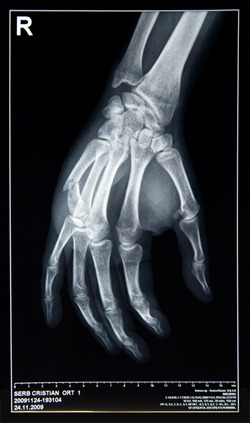

4. criserb 24 Nov 2009 @ 23:58

@Blonda – sa invete lumea ce poti sa patesti daca esti nervos :((

@Pavel – iti dai seama dupa o radiografie, nici eu nu credeam, am crezut ca e doar luxata. M-am dus la doctor dupa 24 ore de gura Danei, nici nu ma gandeam ca e rupta :(

@sby – 3 saptamni minim :(((